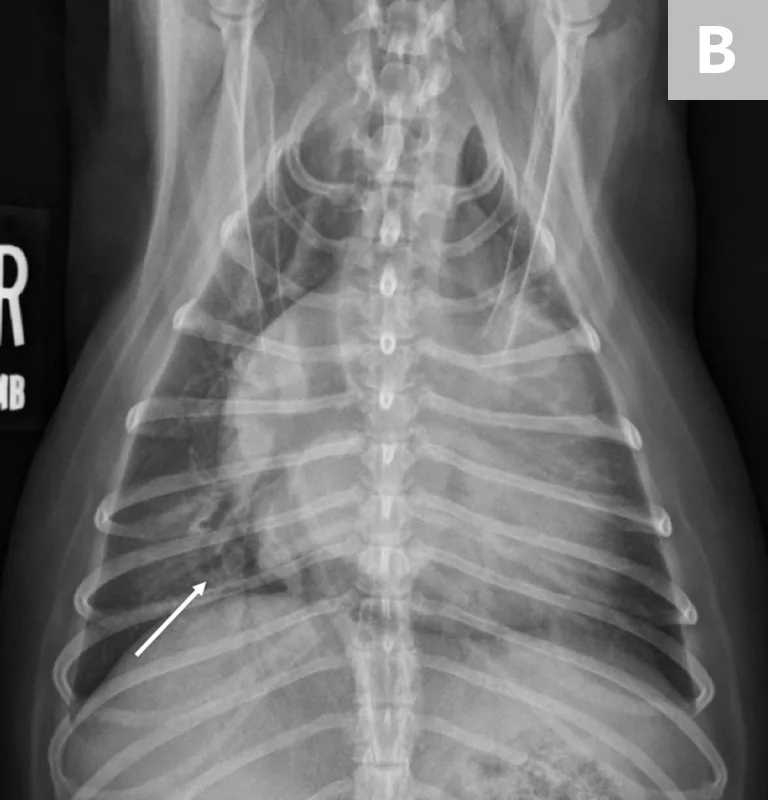

FIGURE 1

(A) L-CHF in a Cavalier King Charles spaniel with mitral valve disease. Enlarged cranial lobar vessels are marked by the arrows. Enlarged left atrium is marked with an asterisk. (B) DV projection shows a caudal interstitial-to-alveolar pattern with air bronchograms (arrow). Images courtesy of University of Florida Small Animal Hospital

In cats, a ventral or diffuse interstitial-to-alveolar pattern may be present3,5; pleural effusion is indicated by pleural fissure lines, retraction of the lung lobes, and effacement of the cardiac silhouette.6 (See Figure 2.) Dyspneic cats with evidence of pulmonary infiltrates should receive a presumptive diagnosis of cardiogenic pulmonary edema until proven otherwise (often by a clinical diuretic trial).